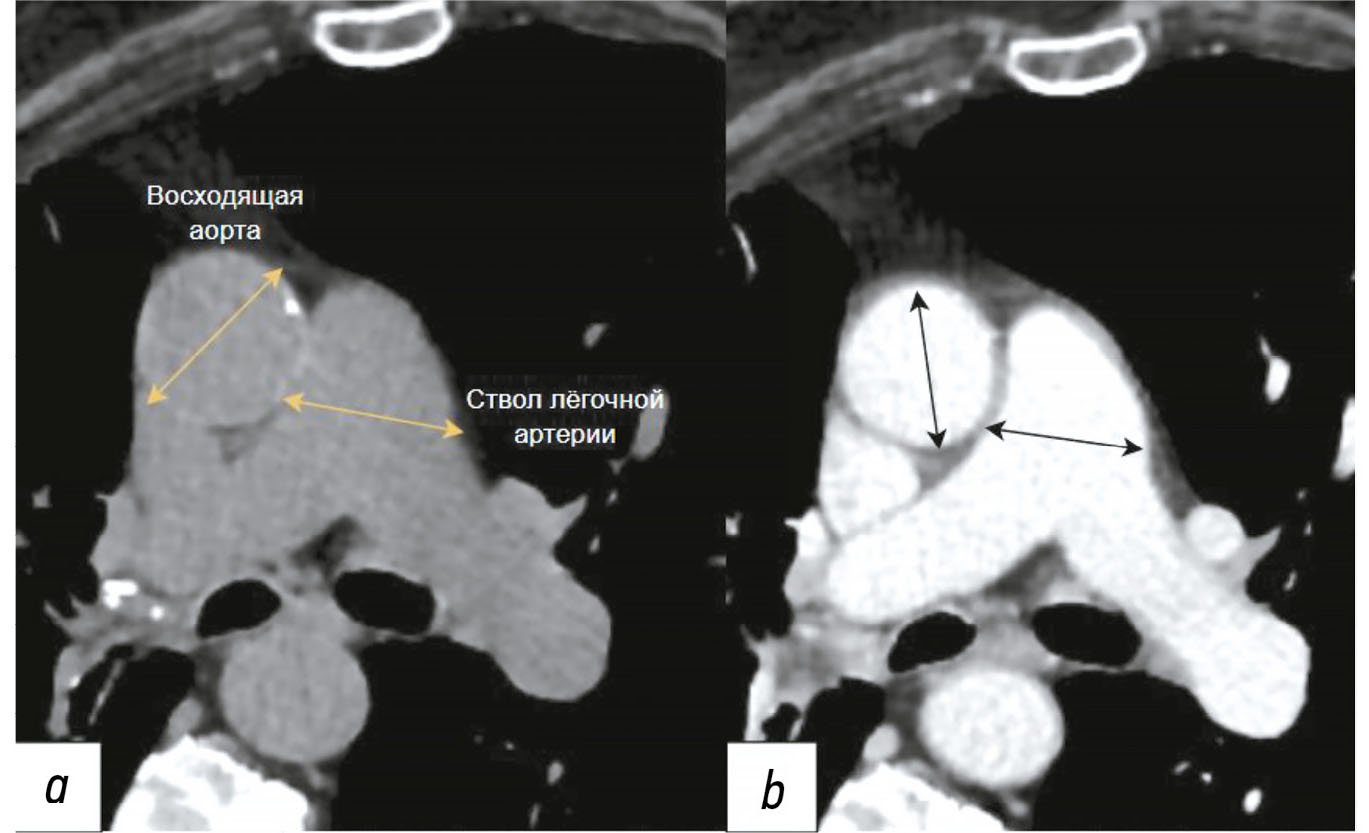

Diagnosis of thoracic aortic aneurysms and pathological pulmonary trunk dilation using chest computed tomography and artificial intelligence: modern approaches and prospects (a review)

Аннотация

Early diagnosis of thoracic aortic aneurysms and pathological pulmonary trunk dilation is crucial to prevent severe complications, including vascular wall rupture and acute right ventricular failure, and reduce cardiovascular mortality. This review examines contemporary imaging approaches for these conditions, focusing on computed tomography as the gold standard modality. Emphasis was placed on the implementation of artificial intelligence technologies, which enable automatic segmentation of vascular structures, measurement of their diameter, and opportunistic screening, allowing early detection of asymptomatic conditions without additional diagnostic procedures, thereby reducing radiologist workload and improving medical care quality. The study comprehensively analyzed the Moscow Experiment, wherein the application of artificial intelligence in medical image analysis showed high sensitivity, reproducibility, and reduced reporting time. Despite these significant advantages, the need for expert supervision of artificial intelligence-generated results to ensure diagnostic accuracy and reliability is emphasized. Moreover, the review highlights the importance of adapting algorithms to different scanning protocols and population-specific features. Additionally, the importance of interdisciplinary collaboration among cardiologists, radiologists, data scientists, and software developers for the effective integration into routine clinical practice is pointed out. Therefore, the review outlines the potential of artificial intelligence technologies to enhance diagnostic quality and underscores the need for further clinical research and standardization of methods for successful integration into daily practice.

286-301